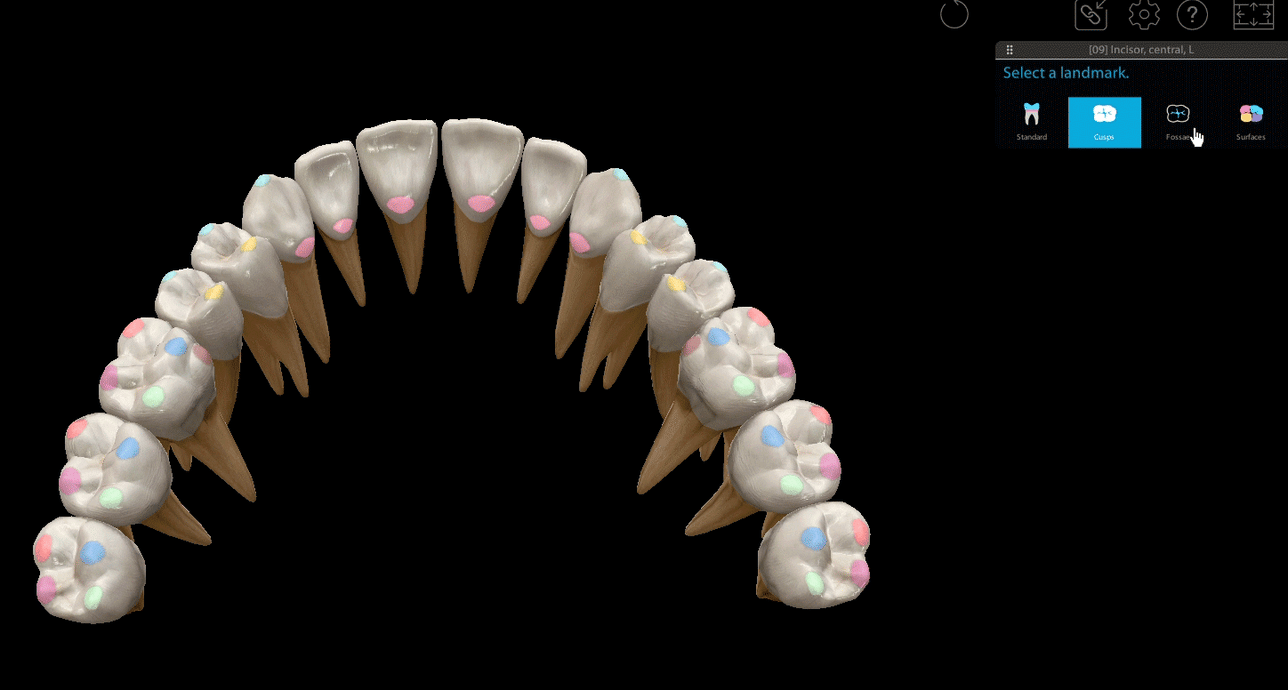

From pocketdentistry.com

Digital Workflow in Oral and Maxillofacial Surgery Pocket Dentistry Dental Anatomy Ct Gaining knowledge of which imaging protocol to use, the relevant anatomy of the teeth and related structures, and the key imaging findings of dental emergencies will help radiologists identify infections, trauma, and complications of dental procedures. Cone beam computed tomography uses an imaging scanner designed for imaging the head and neck and can produce 3d scans of the maxillofacial skeleton.. Dental Anatomy Ct.